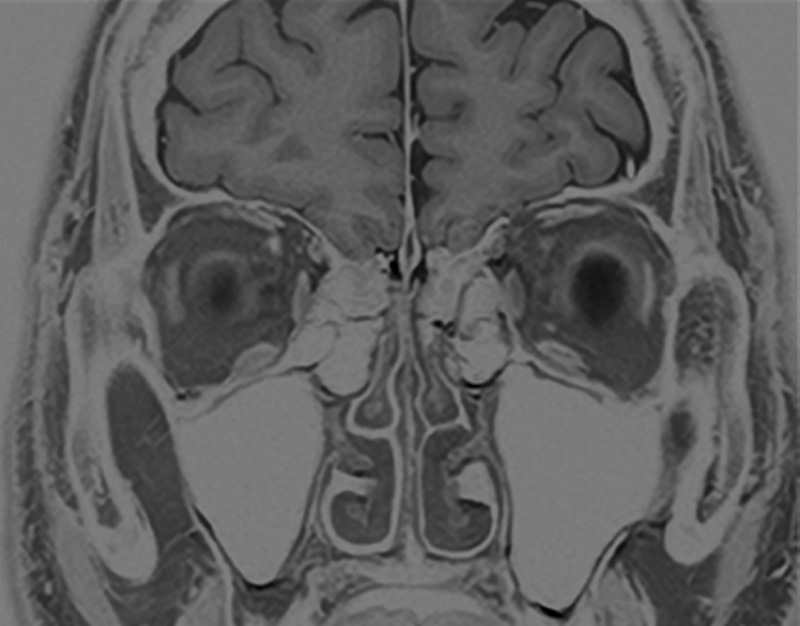

Cor T2w for hippocampus

Example of a high-resolution image of the hippocampus using Precise IQ Engine (PIQE). The original image is 256 matrix with low resolution and high signal-to-noise ratio (SNR).

Even though the scan time is reasonably short and the slice thickness is as thin as 2 mm, the image is clear and demonstrates good contrast.